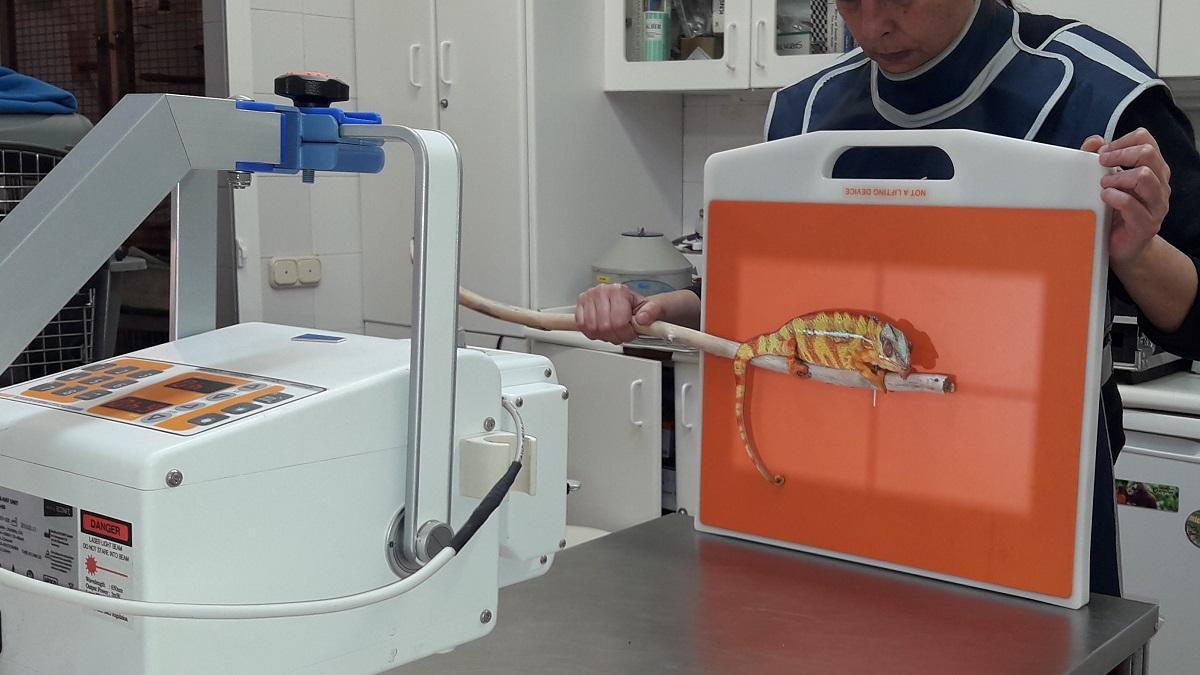

Como indica Rosa Martínez, veterinaria en Bioparc Fuengirola, “los animales considerados peligrosos para su manejo requieren de un proceso de anestesia previo a la toma de radiografías. Por ejemplo, un tigre de Sumatra no va a prestarse voluntariamente a la realización del estudio. Es necesaria una inmovilización previa, normalmente con anestesia general, para realizar estas pruebas diagnósticas”.

Radiografía de un camaleón de Biopark Fuengirola. / L. O.

Sin embargo, otros animales no necesitan de esta inmovilización química para hacerles radiografías. Es el caso de los armadillos. Con ellos basta con un manejo físico y una buena colaboración voluntaria por su parte. “En ocasiones nos valemos de un proceso de entrenamiento previo que llamamos ‘entrenamiento médico’, en el que el animal recibe una recompensa si nos permite realizar estos estudios de manera voluntaria, sin sujeción física y sin anestesia”.

Por supuesto, para la realización de todo procedimiento diagnóstico o manejo veterinario, el equipo de Bioparc Fuengirola se asegura de que los animales no sufran ningún tipo de estrés adicional al examen médico, rutinario o de urgencia. Y no solo los animales, también los veterinarios y los cuidadores están, en todo momento, protegidos con equipos de protección radiológica, que minimizan los efectos de los rayos x en el operador/es del equipo y en el propio paciente.